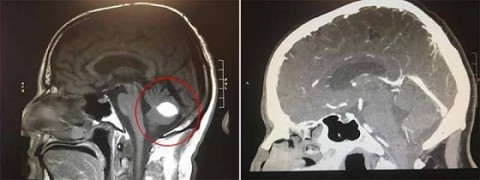

Wood postou em sua conta no Facebook uma tomografia computadorizada de sua cabeça que foi feita no hospital.

"Isso foi em julho de 2018, no canto inferior direito você pode ver o tumor no lugar do círculo branco, agora ele desapareceu”, disse o padre californiano.